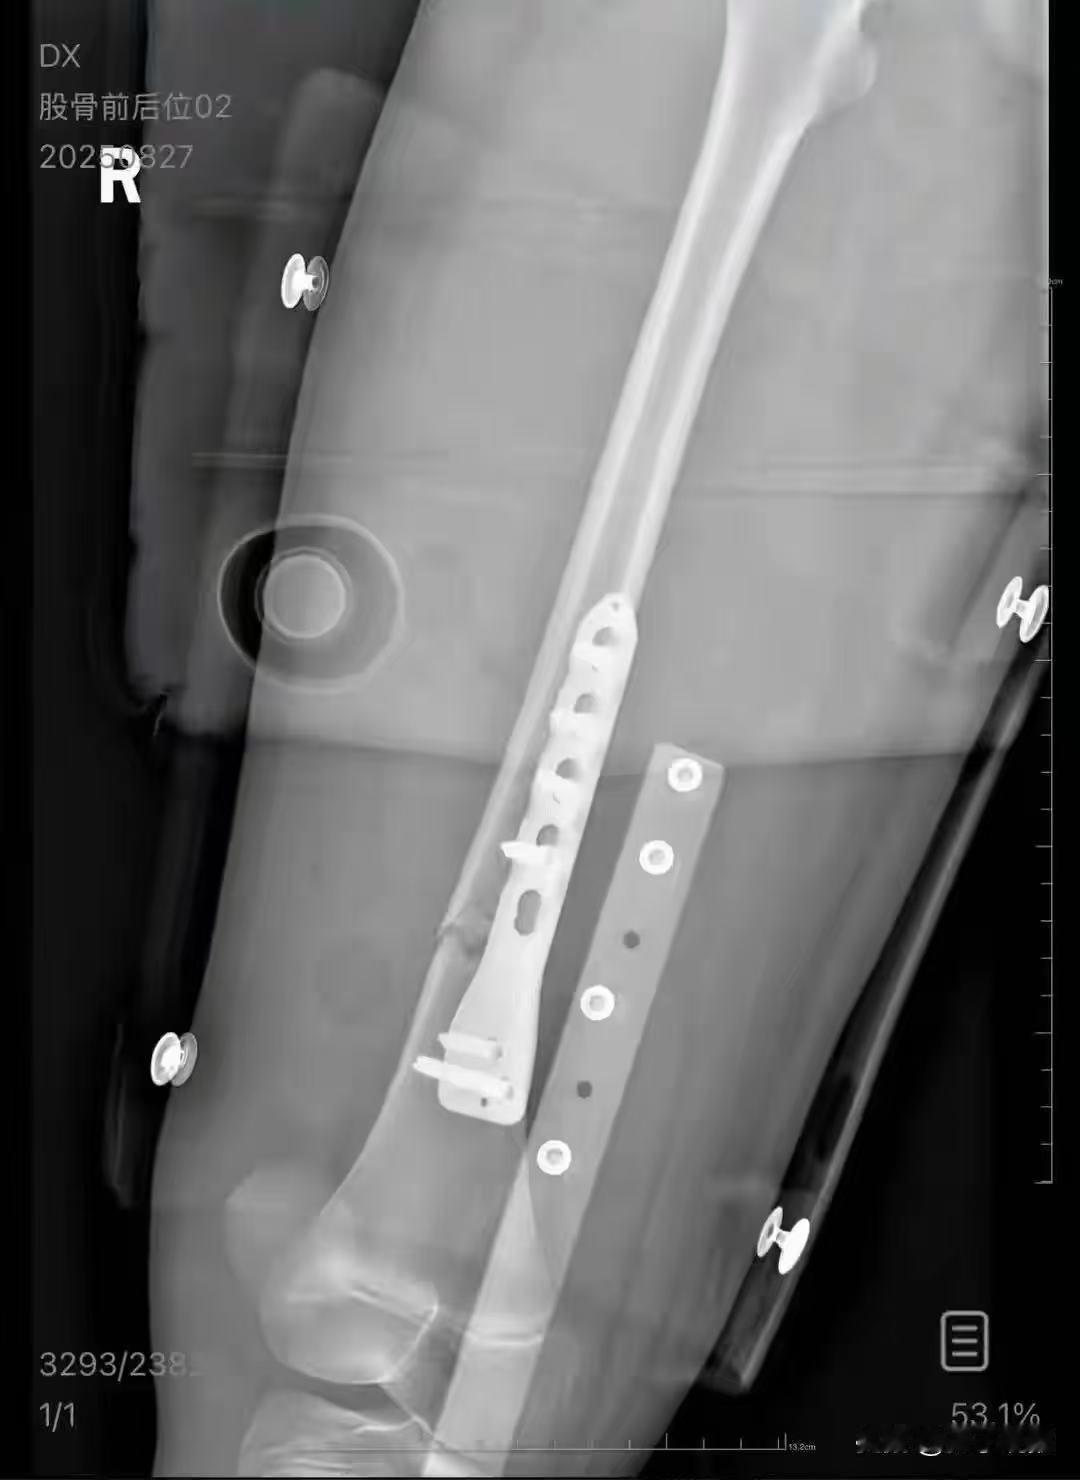

男子从火车上铺跌落砸伤10岁女孩致骨折,女孩母亲:他称回去筹钱,接了一次电话后失联,将通过法律途径维权 网友评论: 这个跟铁路无关,完全是男方的责任,我看了片子,是单纯横形骨折,如果水平高的话,完全可以手法复位,也不需几个钱,手术钢板固定当然有后遗症,你看医疗技术多么重要啊。 任何一个医院的骨科都可以给孩子复位打石膏就行了,因为是单纯的骨折,不是粉碎性骨折,这是医院创收的恶果。孩子根本不用遭这么多罪。 出院后给孩子做伤残鉴定, 等级大概7-10级,按照无锡的规定,伤残赔偿金大概12万到40多万,医疗费等其他费用另算。将那个男的和铁路公司作为共同被告,切记不调解,胜诉百分百 10岁女童和母亲,在一张卧铺上,是否符合铁路运输的规定呢?在此处事故中,铁路部门应该承担什么责任呢